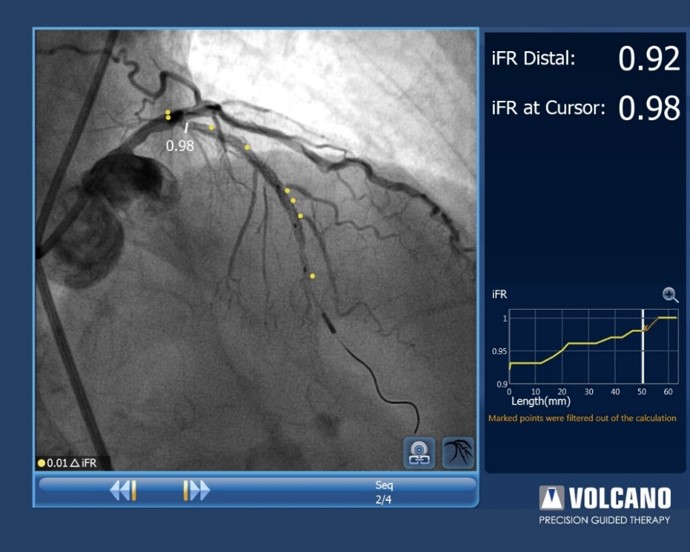

Mit der iFR Ko-Registrierung erübrigt sich die Anwendung hyperämieerzeugender Medikamente. Es bedarf weder eines zeitaufwendigen Rückzugsgeräteeinsatzes, noch einer lediglich geschätzten Übersetzung der physiologischen Rückzugskurve auf den Gefässverlauf.

Die iFR Ko-Registrierung ordnet bildlich den iFR-Verlust entlang der Gefässdarstellung im Angiogramm zu und hebt so ischämieverursachende Gefässabschnitte hervor.

Die iFR Ko-Registrierung ist für die Distanz kalibriert, so dass Sie mit einem einfachen manuellen Rückzug die Messungen im Angiogramm sowie auf der Trendkurve vornehmen können.

„Click and drag“-Messungen helfen bei der Planung der Prozedur